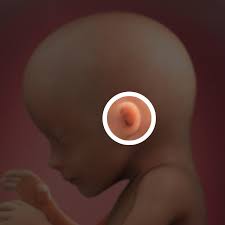

Pregnancy baby womb baby in womb teratogenicity illustration fetal development week 9 baby unborn pregnant of twins pregnancy week 4 baby in uterus embryo baby womb. I just saw the picture after 3 years and looked up fetal images at 8 weeks and somehow stumbled upon this tragic video. At 15 weeks, roman and other preborn children just need a handful of weeks to grow in their mother's wombs until they reach viability. Suction aspiration, or vacuum curettage, is the abortion technique used in most first trimester abortions. See fetus stock video clips. After meeting while praying on the sidewalk of an abortion facility, edward garcia, a single father of two, and i, a single mother of two, married. And the height is about 12 cm. When life published lennart nilsson's photo essay drama of life before birth in 1965, the issue was so popular that it sold out within days. Miscarried at 13 weeks and 4 days, baby nathan isaiah's short life inside the womb affirms the humanity of the preborn at the earliest stages of life. Baby development at 17 weeks. This photo shows a baby at 16 weeks of gestation during the second trimester of pregnancy. Week 17 of your pregnancy. Our content is doctor approved and evidence based, and our community is moderated, lively, and welcoming.

The baby begins to develop translucent skin. Pregnancy baby womb baby in womb teratogenicity illustration fetal development week 9 baby unborn pregnant of twins pregnancy week 4 baby in uterus embryo baby womb. Mother's powerful photos of baby miscarried at 16 weeks show humanity of preborn children. The size of the fetus at 17 weeks pregnant. Beyond the eighth week of pregnancy, the embryo is called a fetus. Incredible real photos of the human developing in the womb. Length, 10 3/4 inches, crown to rump; This photo shows a baby at 16 weeks of gestation during the second trimester of pregnancy. Suction aspiration, or vacuum curettage, is the abortion technique used in most first trimester abortions. Big bellies at 17 weeks 3 days pregnant. The average weight of a baby is about 135 g. Week 17 of your pregnancy. The mirror reports brooklen nicole spent more than 24 weeks in the womb, but a problem with her placenta.

The baby begins to form a substance called meconium, which is the first bowel movement. Our content is doctor approved and evidence based, and our community is moderated, lively, and welcoming. Where is the baby located at 17 weeks pregnant? When you're 17 weeks pregnant, the fetus is about the size of a pear! And the height is about 12 cm. The mirror reports brooklen nicole spent more than 24 weeks in the womb, but a problem with her placenta. At 8 weeks, the baby looks even more human. Babycenter is committed to providing the most helpful and trustworthy pregnancy and parenting information in the world. This photo shows a baby at 16 weeks of gestation during the second trimester of pregnancy. You'll have your second scan, known as the 'fetal anomaly scan' between 18 and 21 weeks. At 10 weeks, the fetus has a very recognizable. If you had to deliver prematurely now, there is a good chance the baby. Suction aspiration, or vacuum curettage, is the abortion technique used in most first trimester abortions.